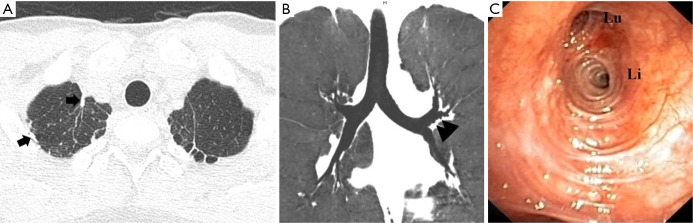

Physical examination was unremarkable. The patient was 178 cm tall and weighed 64 kg but did not have a marfanoid appearance. Pulmonary function test was normal. Computed tomography (CT) of the chest revealed multiple small subpleural blebs/bullae in the left apical lung (Figure 1A). In addition, there were multiple tiny out-pouching lesions arising from the lobar and segmental bronchi of all pulmonary lobes (Figure 1B). There was no evidence of basilar panlobular emphysema. Bronchoscopic examination confirmed the presence of diffuse bronchial diverticulosis involving multiple lobar and segmental bronchi, bilaterally (Figure 1C).

Figure 1.

(A) Thin-section axial CT scan of the chest with lung-window setting showing multiple small residual subpleural blebs/bullae at the left lung apex. Note fibrotic scarring at the bilateral lung apices and several staples (arrow) at the right apex as a result of prior thoracotomies; (B) coronal CT image of the tracheobronchial tree obtained with minimum intensity projection technique and lung window setting showing multiple tiny diverticula (arrowheads) arising from the left upper lobe bronchus and its segmental bronchi; (C) bronchoscopy revealing bronchial diverticulosis, seen as multiple tiny dimples or mucosal depressions in the left upper lobe bronchus and at the origins of its upper division (Lu) and lingular bronchus (Li).